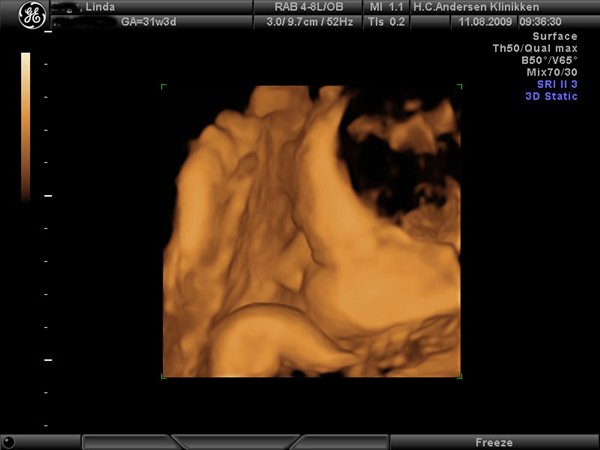

Jeg har lige været til en 3D/4D scanning (27+0), hvilket var en kæmpe oplevelse. Jeg venter en dreng på foreløbig 976 gram

Denne tråd er for alle os som har fået foretaget sådan en scanning. Jeg tænkte det kunne være sjovt at smide nogle fotos op af vores bebzere, da de lå i maven. I profil og forfra.

Skriv gerne hvilken uge scanningen er foretaget, samt evt. hvad køn det er